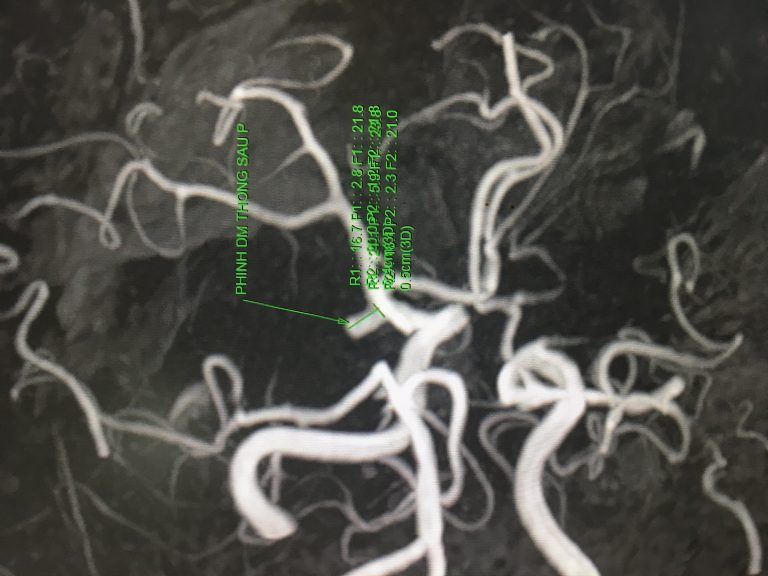

Phát hiện phình mạch ở bênh nhân đau đầu khi chụp MRI (không tiêm thuốc).